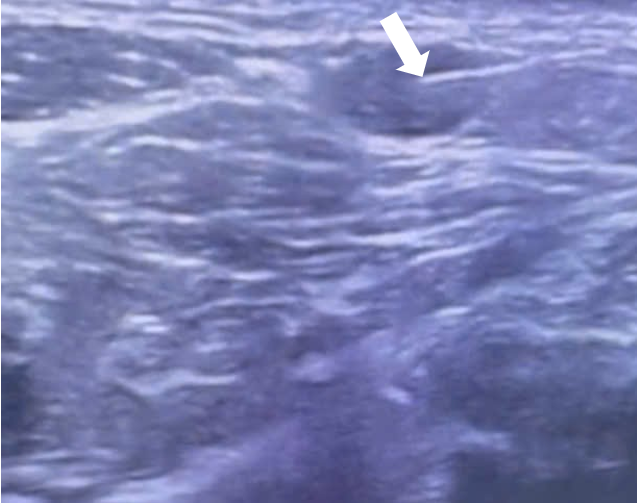

Đầu kim (mũi tên trắng) đi vào hạch dưới siêu âm